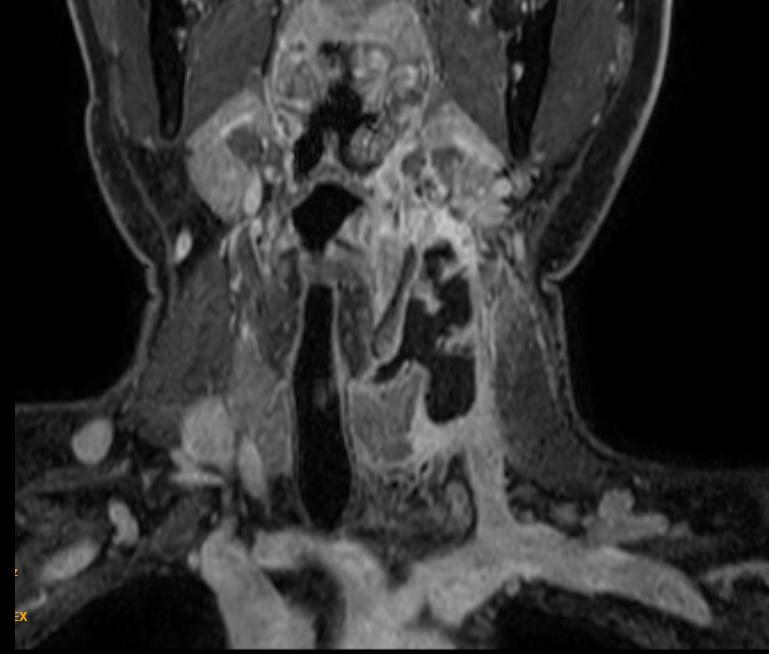

一周前,孙先生左侧颈部再次肿胀起来,孙先生很疑惑,同一个地方反复化脓感染,会不会还有其它问题?带着这个疑问,孙先生来到龙华区人民医院就诊。经龙华区人民医院耳鼻喉科钱迪、陈志喜主任医师仔细检查后,考虑可能是颈部一种相对罕见的疾病——先天性梨状窝瘘(又名:第三鳃源性瘘管)伴感染可能性大,建议孙先生进一步完善颈部增强磁共振检查。

先天性梨状窝瘘( Congenital pyriform sinus fistula,CPSF)是临床上少见的颈部鳃源性疾病。因为这种疾病较少见,并且瘘管的走行复杂,国内的相关医学文献更是缺乏,从而导致认知的有限和诊治经验的严重不足,临床上经常误诊误治,病情迁延不愈几乎成为此类疾病的“主旋律”。其包括第三和第四鳃裂畸形, 占所有鳃源性畸形的 l% - l5%,为胚胎发育早期咽囊或鳃弓异常穿破或不完全闭锁所形成。95%患者的病变发生在左颈,可能与胚胎早期双侧鳃弓发育不对称C细胞迁移紊乱有关。先天性梨状窝瘘(CPSF) 的典型表现是反复发作的颈部脓肿。颈部蜂窝织炎和急性化脓性甲状腺炎等。患者以颈部瘘口伴或不伴溢出液体、豆腐渣样物或者颈部肿块,肿胀、流脓、发热等临床表现入院。